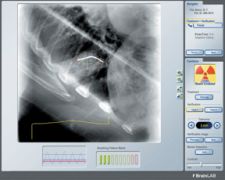

Photo courtesy of BrainLAB Inc.